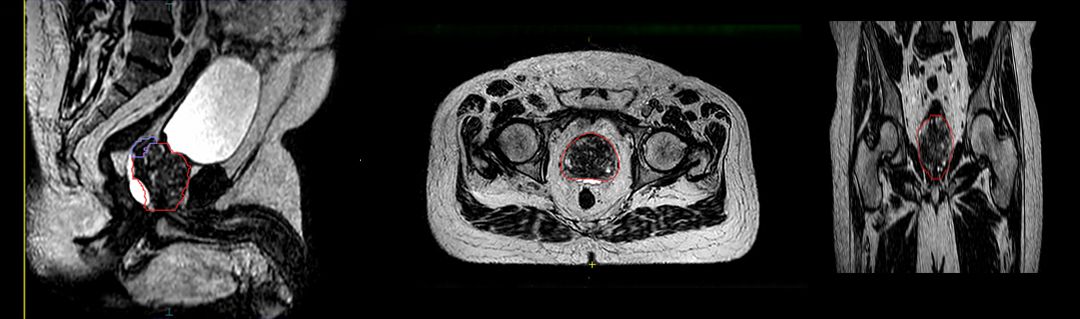

The Froedtert & MCW Clinical Cancer Center’s acquisition of Elekta Unity in 2019 changed the imaging equation of prostate radiotherapy dramatically. It provided pristine, MR-quality visualization of anatomy compared to CT, thereby improving the delineation of the prostate. In addition, it gave clinicians the ability to create treatment plans on the MR-Linac, enabling the treatment to be shaped to the patient’s anatomy in the treatment position just before therapy delivery.

“Being able to modify the treatment just before beam delivery is a big advantage over the standard radiotherapy workflow, which just takes an anatomical snapshot during simulation,” she notes. “That could be two weeks before treatment, and a lot can change anatomically in that time. With Elekta Unity, we’re also able to watch the image during beam delivery, which is important in prostate radiotherapy because the gland can be displaced by bladder and bowel contents during the fraction.”

With Elekta Unity, the quality of the planning images and real-time imaging during beam delivery enable Froedtert & MCW Clinical Cancer Center clinicians – for select prostate patients – to use a moderately hypofractionated schedule of 60 Gy delivered in 20 fractions over four weeks [i.e., PRISM protocol6].

“Especially with SBRT that uses these very high-dose fractions, Elekta Unity enables us to actually watch bowel gas come through and stop beam delivery if it looks like things are really moving,” she says. “Even in a situation in which you’re using implanted fiducial markers with a conventional system, deformation can occur in the prostate where the fiducials may not change a lot, but the actual outside of the gland has moved. You won’t be able to see that except on a system like Elekta Unity.”